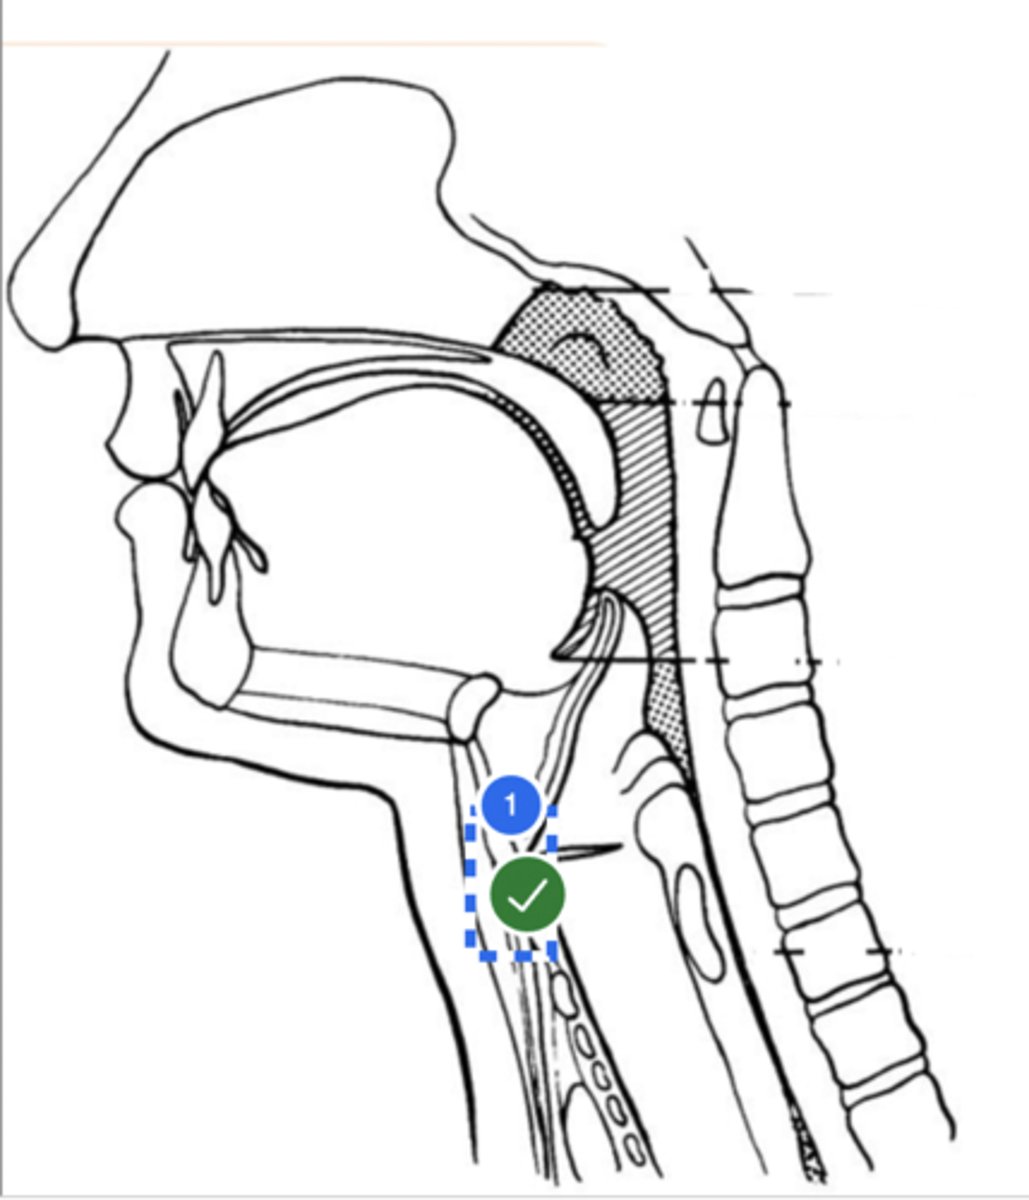

Label base of tongue (lateral view)

label anterior tongue (lateral view)

Label posterior/ back of tongue (lateral view)

Label Mandible (lateral view)

Label velum/ soft palate (lateral view)

Label hyoid bone (lateral view)

Label epiglottis (lateral view)

Label thyroid cartilage (lateral view)

Label posterior cricoid (lateral view)

Label trachea (lateral view)

Label upper esophageal sphincter (lateral view)

Label esophagus (lateral view)

Label posterior pharyngeal wall (lateral view)